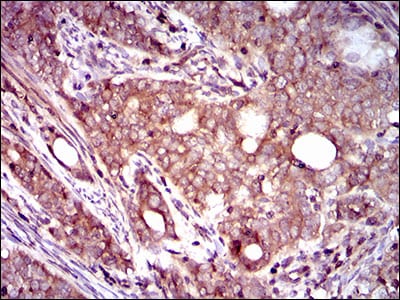

分类: 科研抗体货号: 30470P别名: HIWI2; MIWI2应用: WB,IHC,FCM反应种属: Human

分类: 科研抗体货号: 30470A别名: HIWI2; MIWI2应用: WB,IHC,FCM反应种属: Human